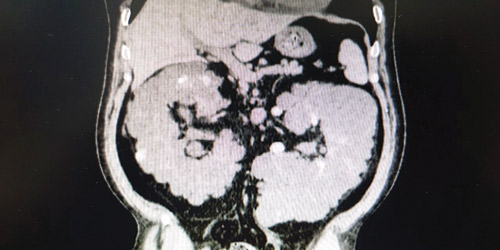

تمكن الفريق الطبي بقسم المسالك البولية بالمستشفى السعودي الألماني بالرياض من إنهاء معاناة مريض من آلام شديدة بالبطن، باستئصال الكلية اليسرى التي كانت متعددة الأكياس بحجم يتجاوز الـ30 سنتيمترًا والتي كانت سببًا مباشرًا في معاناة المريض بشكل دائم من آلام شديدة في البطن وارتفاع في درجات حرارة الجسم. وكان المريض صاحب الـ 48 عامًا قد قدم إلى استقبال المستشفى وهو يعاني آلاماً شديدة في البطن، مع ارتفاع في درجة الحرارة.

وبعد إجراء الفحوصات اللازمة تبين وجود أكياس متعددة ممتلئة بالصديد والتجمعات الدموية بالكلية اليسرى، وعلى الفور قرر الفريق الطبي إجراء جراحة عاجلة لاستئصال الكلية اليسرى والذي تم بنجاح وهو الأمر الذي أدى إلى تحسن عمل الكلية اليمنى وعودة نشاطها، وقد كان المريض يقوم بعمل غسل كلوي قبل ذلك. وعلى إثر ذلك خرج المريض من المستشفى بحال أفضل بعد إجراء العملية.